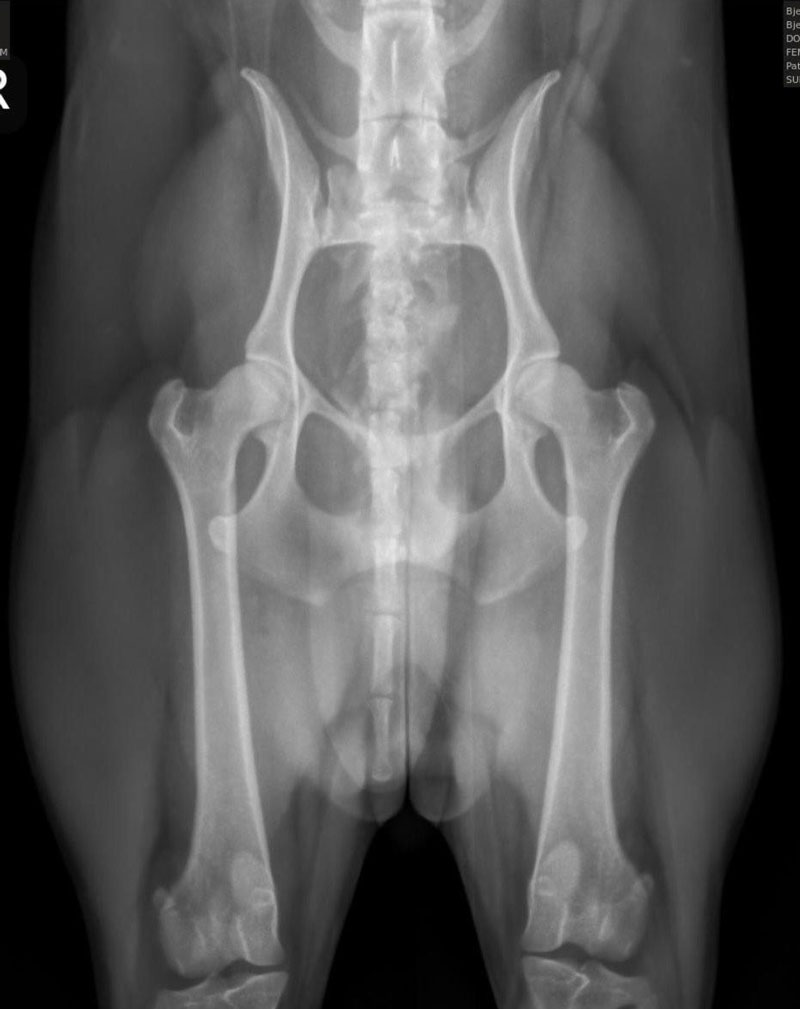

We are proud to offer state of the art Idexx radiology technology and equipment, which allows the clearest of images to be provided to our clientele. This is especially helpful when needing to determine final puppy count prior to whelp. The best time to perform a pregnancy radiograph is 55 days or later from breeding. An appointment is required for this service.

We are also proud to offer OFA (Orthopedic Foundation for Animals) image submissions. This is a requirement amongst many AKC breed clubs and may include several different image types such as:

We frequently receive inquiries regarding our success with proper positioning for OFA images, specifically for hips. Translating this success can be challenging, so we have included images of various breeds that we have taken. We take great pride in our success with these images and many others like them. As extreme perfectionists, we appreciate owners who understand that we strive for the best technique and outcome while minimizing stress and ensuring the comfort of your dog(s), particularly since all images taken here are done WITHOUT sedation.